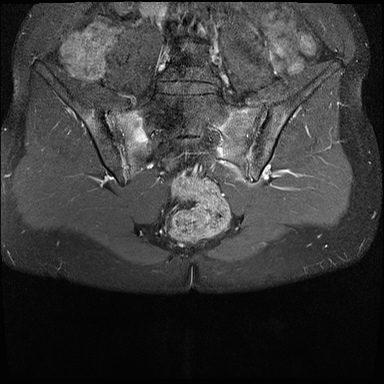

MRI

MRI chuỗi xung T1W sau tiêm thuốc tương phản từ của cùng bệnh nhân cho thấy bờ khớp cùng chậu không đều do bào mòn.

Có ngấm thuốc ở xương dưới sụn và phù nề tủy xương.

Không có tràn dịch khớp.

Thuốc tương phản từ tiêm tĩnh mạch không nhất thiết phải sử dụng để chẩn đoán viêm khớp cùng chậu.

Cuộn qua các hình ảnh MRI và so sánh với các dấu hiệu trên X-quang (hình ảnh cuối cùng).